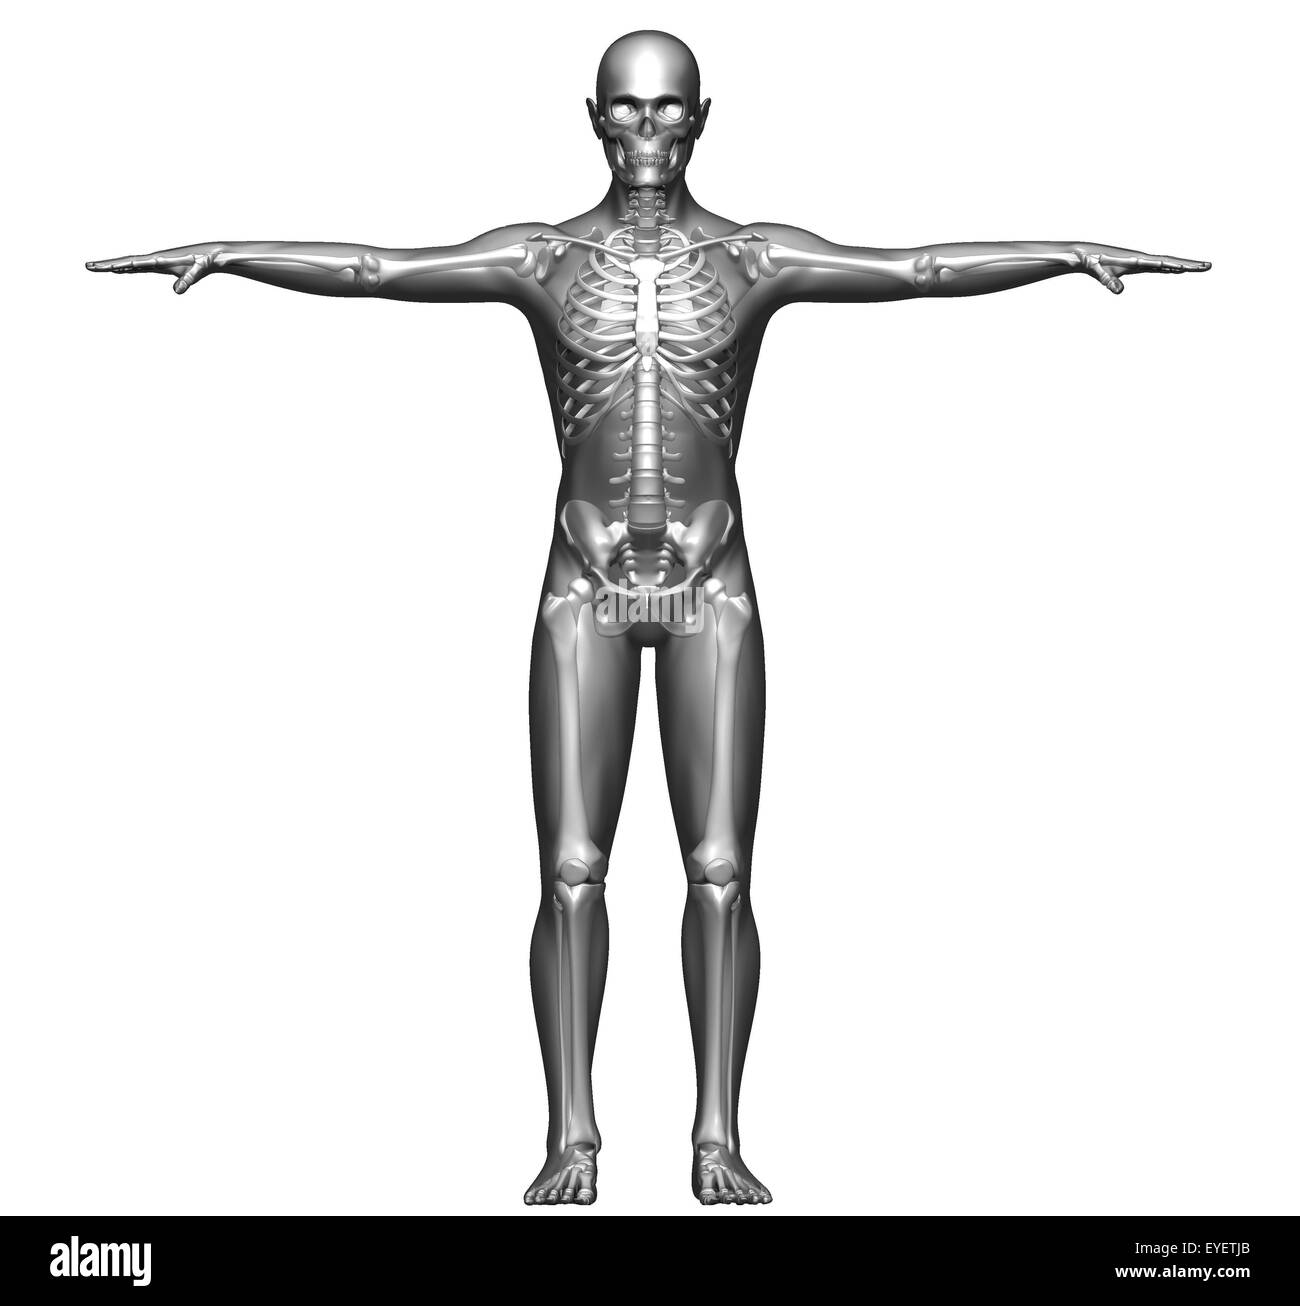

Xray, X-ray Of The Human Male Body. Royalty Free Stock Photos – Image …

Xray, X-ray Of The Human Male Body. Stock Illustration – Illustration …

Front view x-ray of a human body and skeleton Stock Photo – Alamy